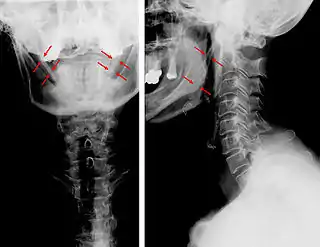

Vistas lateral y anteroposterior de una radiografía cervical que muestra osificación del ligamento estilohioideo. | ||

El diagnóstico se realiza en base a los signos y síntomas descritos y debe ser confirmado mediante pruebas de imagen. Los síntomas suelen empeorar en la palpación de la apófisis estiloides.[10]

La apófisis alargada o calcificación del ligamento estilohioideo suelen mostrarse fácilmente a través de una prueba radiográfica. De forma adicional se puede realizar un TAC para confirmar el diagnóstico y ver qué estructuras están siendo afectadas.[10]